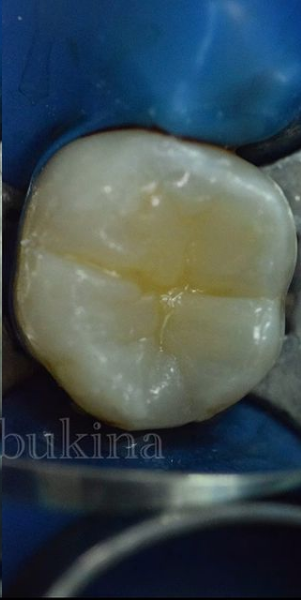

Букина Ольга Сергеевна принимает в стоматологической клинике ЗУБНАЯ ФОРМУЛА в Москве. Специализируется на терапевтии, по которой клиника оказывает 9 услуг. Имеет 6 работ до/после в портфолио. Для уточнения дополнительной информации о специалисте или записи на прием можно позвонить по телефону

Лечение кариеса

Лечение кариеса в Москве